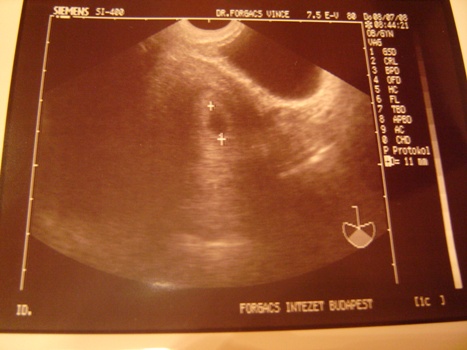

Láttuk Őt!!!! Juhéééjjjj!!! :lol: :lol: :lol: Szívhang még nincs, ahhoz még kicsi, 11mm-es petezacsiban növekszik! :wink: :D Jaaj, annyira boldog vagyok, hogy madarat lehetne velem fogatni! :wink: Kaptam képet is, este majd felteszem! :wink: 2 hét múlva kell mennem legközelebb. :D